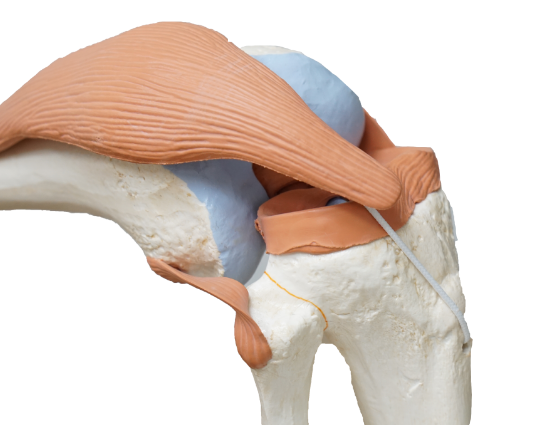

해당 병원에서 무릎수술의 경험이 가장 많으신 의사 선생님께 진료를 받고 상담을 진행하였습니다. 수술을 권유받고 수술 절차와 방법에 대해 설명을 듣고 로봇을 이용한 수술을 선택했습니다. 로봇수술은 절개 부분이 작아 출혈이 적고 회복이 비교적 빠르며 정밀 수술이 가능하다는 장점이 있지만 아무래도 비용이 추가된다는 부담이 있었습니다.

무릎 인공관절 수술은 약 한 시간에서 한 시간 반정도 소요되며 양측 수술일 경우 1차 수술 후 일주일 뒤에 2차 (다른 쪽) 수술이 진행됩니다. 마취는 하반신 마취를 기본으로 하나 환자의 상태에 따라 전신마취를 할 수도 있습니다. 저희 어머니의 경우 수술 후 이틀정도는 통증이 심하셨다고 합니다.